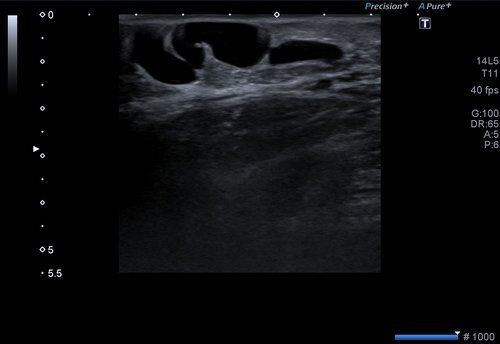

Kol ve bacak toplardamarlarını incelemek için omuz ve kalça düzeyinden başlayarak el ve ayak bileğine kadar olan alan taranır.

Bu alanlarda toplardamarların genişlikleri ölçülür. Bu inceleme ile toplardamarlardaki darlıklar, tıkanıklıklar, pıhtı oluşumu, yetmezlikler değerlendirilir.